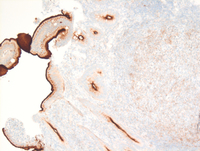

CD20 stain

The nodular aggregates are strongly positive for CD20. In addition, the CD20 positive cells are seen to extend into the villi.